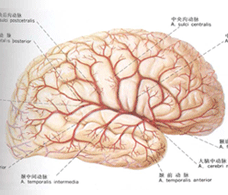

發病機理

導致顱內壓增高征的疾病很多,因此,其發病機理也因不同疾病而異。例如:顱內占位性病變可因其容積的增大 而引起顱內壓增高;腦脊液循環障礙時,發生腦積水,可致顱內壓增高;動脈血二氧化碳分壓增高或嚴重缺氧時,可因腦血管擴張、腦血 流量增加而引起顱內壓增高;嚴重感染或中毒時,可致腦血管通透性增加,腦細胞及細胞間水分增加,形成急性瀰漫性腦水腫,變引起顱內壓增高。